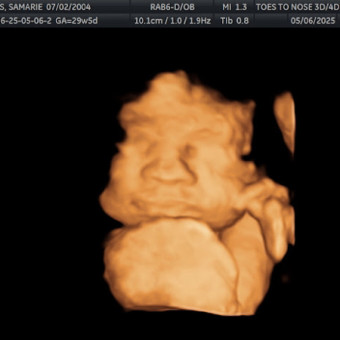

Samarie's Baby Registry

Samarie Peters

Morristown, TN

July 17, 2025